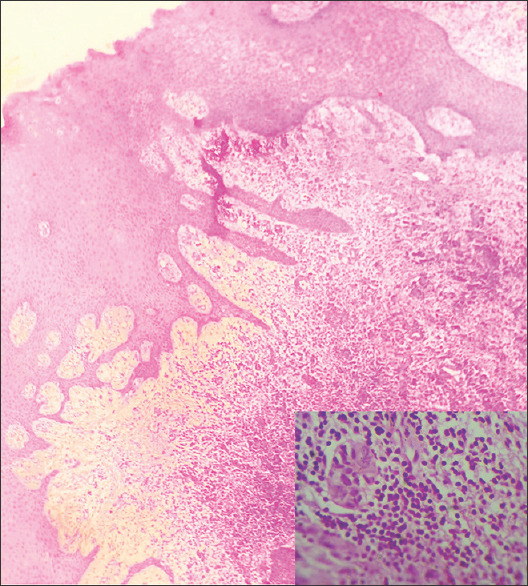

Rosai-Dorfman病(RDD)是一种罕见的组织细胞疾病,典型表现为广泛的淋巴结病变。我们提出一个独特的病例结外RDD在一个14岁的单发上颌病变和轻度双侧下颌下淋巴结病。临床、放射学和组织病理学评估证实了RDD,强调了综合治疗的重要性。免疫组织化学,包括CD68、CD45、cd1a和S100,在诊断中起着至关重要的作用。鉴别诊断包括朗格汉斯细胞组织细胞增多症、厄德海姆-切斯特病、淋巴瘤和组织细胞肉瘤,需要仔细的评估。由于骨受累,手术切除,6个月后成功愈合。我们的病例强调了多学科和科学方法对准确诊断和管理RDD的重要性,特别是在非典型口腔内表现。

Rosai-Dorfman disease (RDD), a rare histiocytic disorder, typically manifests as widespread lymphadenopathy. We present a unique case of extranodal RDD in a 14-year-old with a solitary maxillary lesion and mild bilateral submandibular lymphadenopathy. Clinical, radiological, and histopathological assessments confirmed RDD, highlighting the importance of a comprehensive approach. Immunohistochemistry, including CD68, CD45, CD 1a, and S100, played a crucial role in diagnosis. Differential diagnoses encompassed Langerhans cell histiocytosis, Erdheim-Chester disease, lymphomas, and histiocytic sarcoma, necessitating meticulous evaluation. Surgical excision was performed due to bone involvement, leading to successful healing in six months. Our case underscores the significance of a multidisciplinary and scientific approach for accurate RDD diagnosis and management, especially in atypical intraoral presentations.